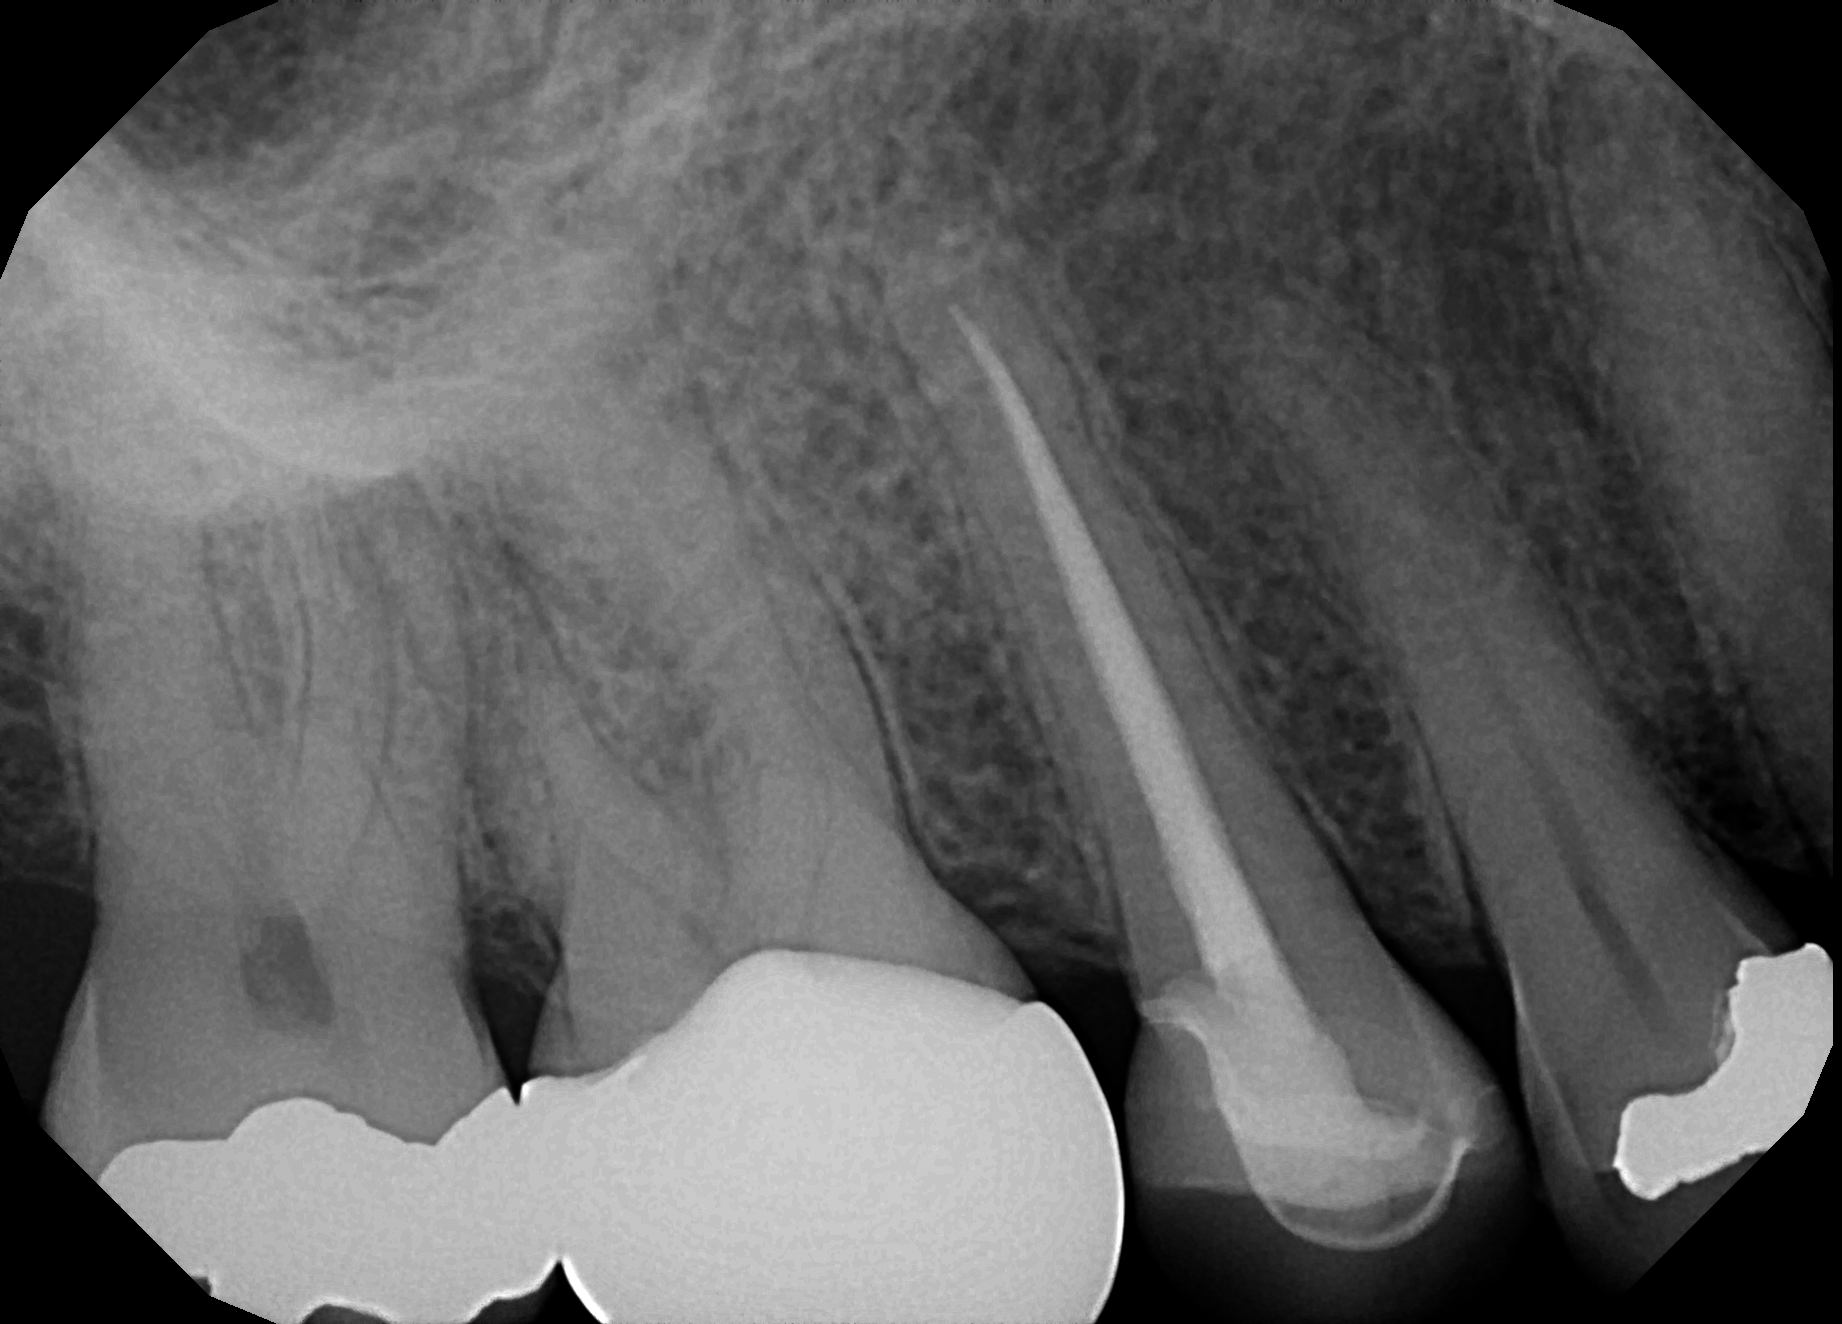

Retreatments What We Do Cornerstone Endodontics Cornerstone Endodontics Cornerstone endodontics offers root canals, endodontic retreatments, and apicoetomy in a comfortable and compassionate environment. Cornerstone endodontics is a specialty practice that offers root canal treatments and other endodontic services in a friendly and. Welcome to our meet the doctors page. We are an extension of your comprehensive dentist’s practice and will strive to make your visit here as comfortable. Cornerstone Endodontics.